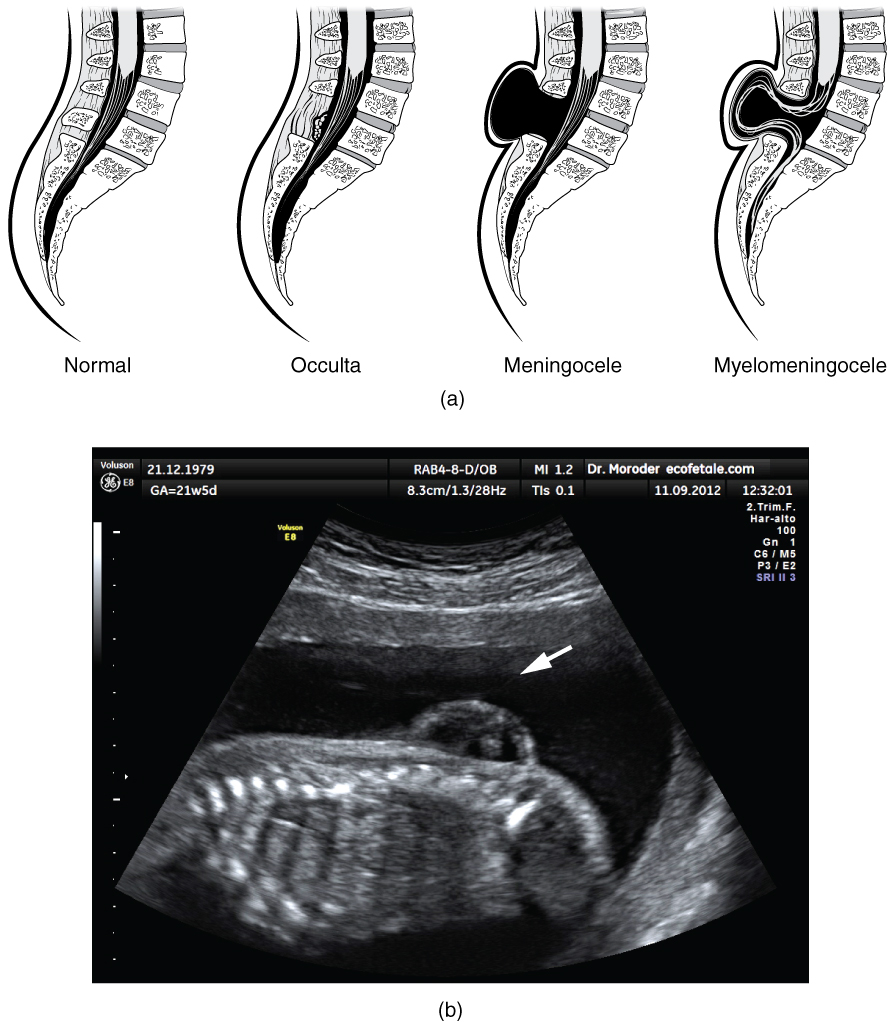

Early formation of the nervous system depends on the formation of the neural tube. A groove forms along the dorsal surface of the embryo, which becomes deeper until its edges meet and close off to form the tube. If this fails to happen, especially in the posterior region where the spinal cord forms, a developmental defect called spina bifida occurs. The closing of the neural tube is important for more than just the proper formation of the nervous system. The surrounding tissues are dependent on the correct development of the tube. The connective tissues surrounding the CNS can be involved as well.

There are three classes of this disorder: occulta, meningocele, and myelomeningocele (Figure 1.4). The first type, spina bifida occulta, is the mildest because the vertebral bones do not fully surround the spinal cord, but the spinal cord itself is not affected. No functional differences may be noticed, which is what the word occulta means; it is hidden spina bifida. The other two types both involve the formation of a cyst—a fluid-filled sac of the connective tissues that cover the spinal cord called the meninges. ā€œMeningoceleā€ means that the meninges protrude through the spinal column but nerves may not be involved and few symptoms are present, though complications may arise later in life. ā€œMyelomeningoceleā€ means that the meninges protrude and spinal nerves are involved, and therefore severe neurological symptoms can be present.

Spinal Bifida

Figure 1.4 – Spinal Bifida: (a) Spina bifida is a birth defect of the spinal cord caused when the neural tube does not completely close, but the rest of development continues. The result is the emergence of meninges and neural tissue through the vertebral column. (b) Fetal myelomeningocele is evident in this ultrasound taken at 21 weeks.